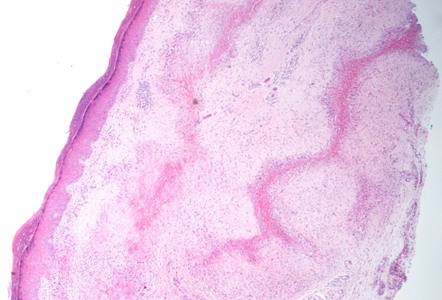

With the diagnostic hypotheses of rheumatoid nodule, granuloma annulare, erythema elevatum diutinum and sarcoidosis, incisional biopsy was performed and histopathological examination showed palisaded epithelioid granulomas in the superficial and deep dermis, without plasma cells, with central fibrinoid necrosis, in addition to vascular ectasia with tumefied endotheliocytes and fibrin thrombi. The process touched the epidermis in foci, suggesting areas of transepidermal elimination (Figures 4 & 5).

Figure 4 H&E, 40x: presence of palisade granulomas with central necrobiosis.

Figure 5 The lesion approaches the epidermis, outlining transepidermal shedding of necrobiotic collagen.